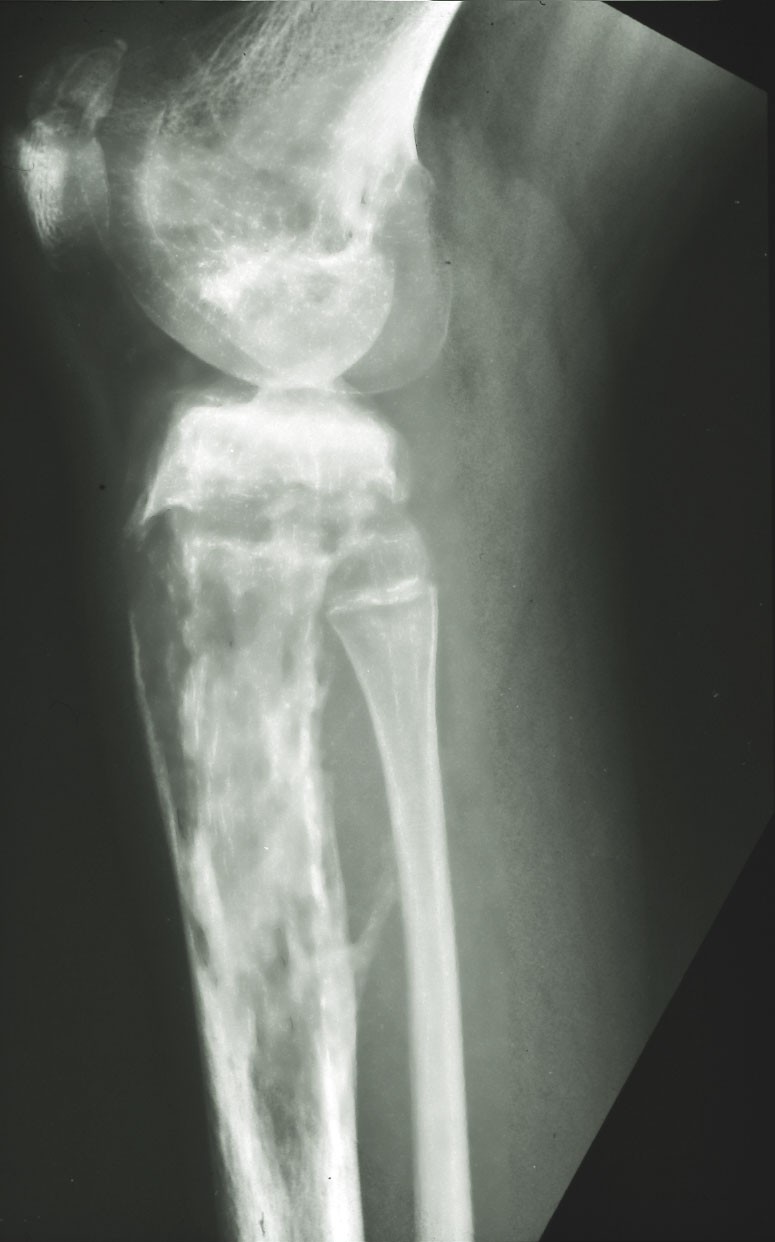

osteosarcoom |

Klinisch beeld:Poikiloderma en teleangiëctasieën

in een fotodistributie, rode en/of oedemateuze plaques, soms met blaarvorming,

op de wangen, billen en extremiteiten, fotosensitiviteit,hyperkeratose op ellebogen,

knieën, handen, voeten, palmoplantaire hyperkeratose. Cataract op jonge leeftijd,

botafwijkingen (korte beenderen, missende duimen, afwijkende vorm gelaat met

uitpuilend voorhoofd, zadelneus, micrognathia), gestoorde haargroei, ontbrekende

wenkbrauwen of wimpers,

vroegtijdig grijs

worden, nagel dystrofie of atrofie, hypodontie, gestoord calcium metabolisme,

calcinosis cutis. Verhoogde kans op

osteosarcoom en huidkanker. Soms anemie, neutropenie, leukemia. Soms ook hypoplasie

genitaliën, amenorroe, infertiliteit.

naar de RECQL4 mutatie. Röntgenfoto's van de extremiteiten vanaf 5 jarige leeftijd.